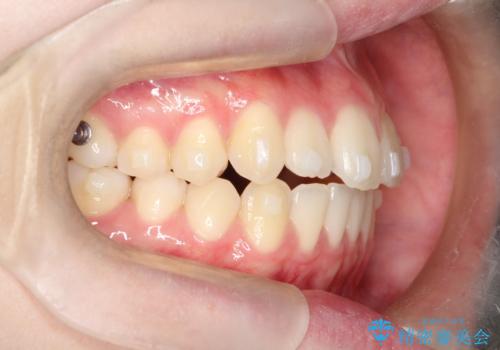

【インビザライン】前歯のガタガタをなおしたい

- 前歯のガタガタを主訴に来院されました。

開咬ぎみであったため、しっかりと前歯が噛むように計画を立てて治療をおこないました。

仕上がりも良く、患者様にも満足していただきました。

インビザラインは前歯を噛ませるような開咬の治療も得意としています。